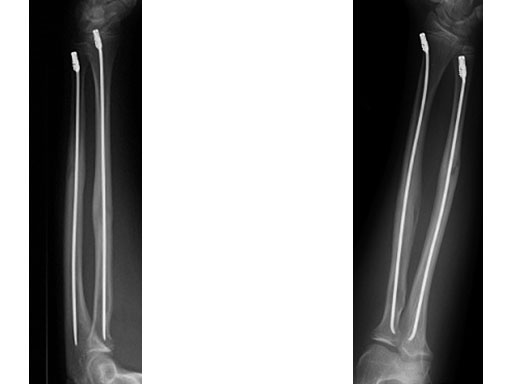

Case 2: Oblique forearm, shaft fracture (22D/5.1) with end caps, 11-year-old boy.

Case provided by Theddy Slongo, Bern, Switzerland